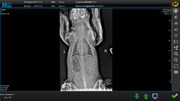

Коллапс трахеи форум

Коллапс трахеи форум 116 фотографий